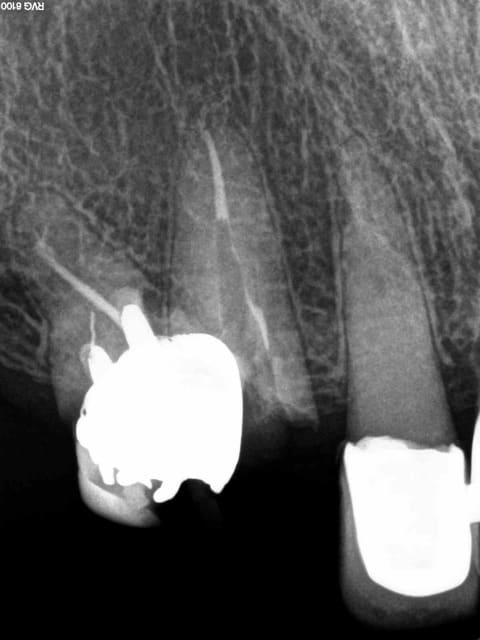

Arrivé un moment ou tu te dis que tu vas l'extraire, mais tu ne le fais pas parceque ca fait 3/4 d'heures que tu cherches ce putain de canal. Et enfin la lumière fut ( c'est le cas de le dire). -)))))

1 nfmvd7 - Eugenol

2 dvdqtt - Eugenol

3 f3ohf3 - Eugenol

4 zmohou - Eugenol

5 j0htr8 - Eugenol

6 e86kdq - Eugenol

7 fbttie - Eugenol